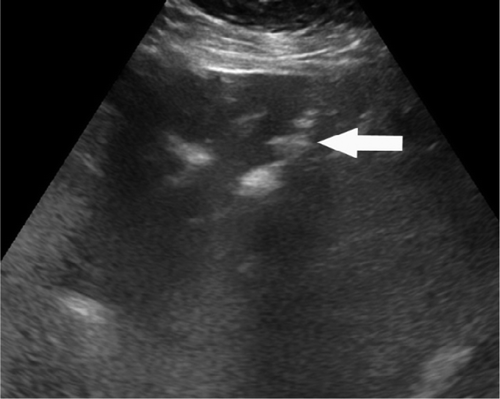

В частности, как пояснил специалист, у некоторых пациентов с COVID-19 внезапно развивался пневматоз - патологическое состояние системы пищеварения, при котором газы проникают в толщу стенки кишечника и образуют там воздушные кисты. Кроме того, у нескольких людей было выявлено необычное желтое обесцвечивание кишечника, еще у трех больных - инфаркт кишечника.

© Radiology